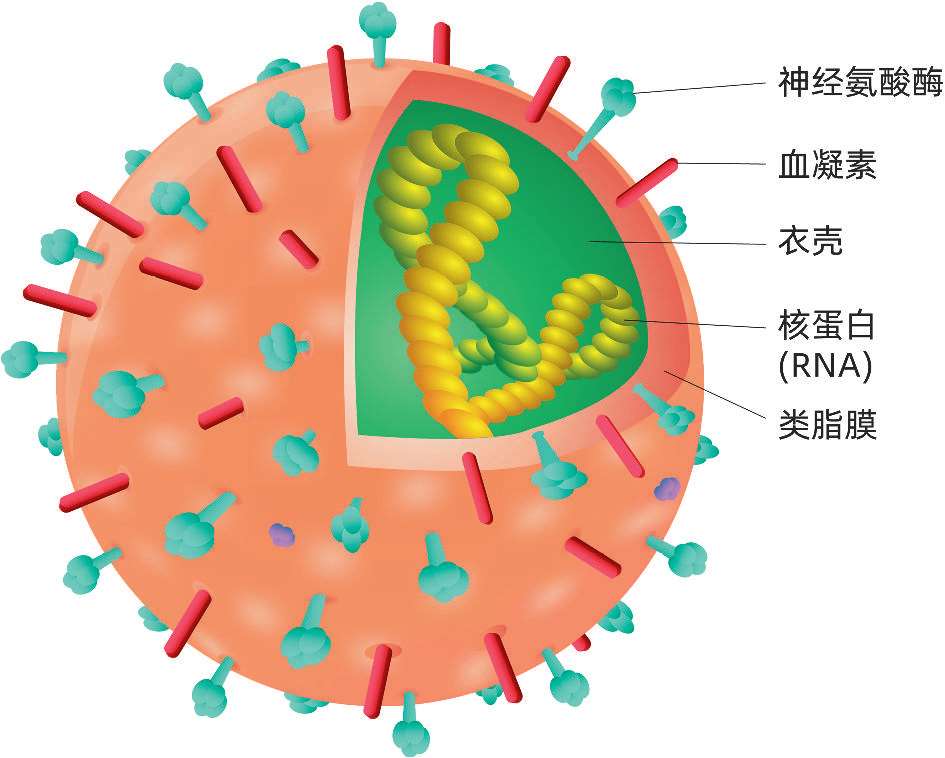

流感是流行性感冒的简称,是由流感病毒引起的急性呼吸道传染病。病毒由包膜、基质蛋白及核心组成。根据流感病毒核蛋白的抗原性,一般将其分为甲(A)、乙(B)、丙(C)三型。

甲型流感病毒传染性强,多为急性起病。

·以发热、畏寒、头痛、肌肉关节酸痛、乏力、食欲减退等全身症状为特征。

·常有咽痛、咳嗽、鼻塞、流涕、呕吐、腹泻等呼吸道合并消化道症状。

·轻症流感常与普通感冒表现相似。